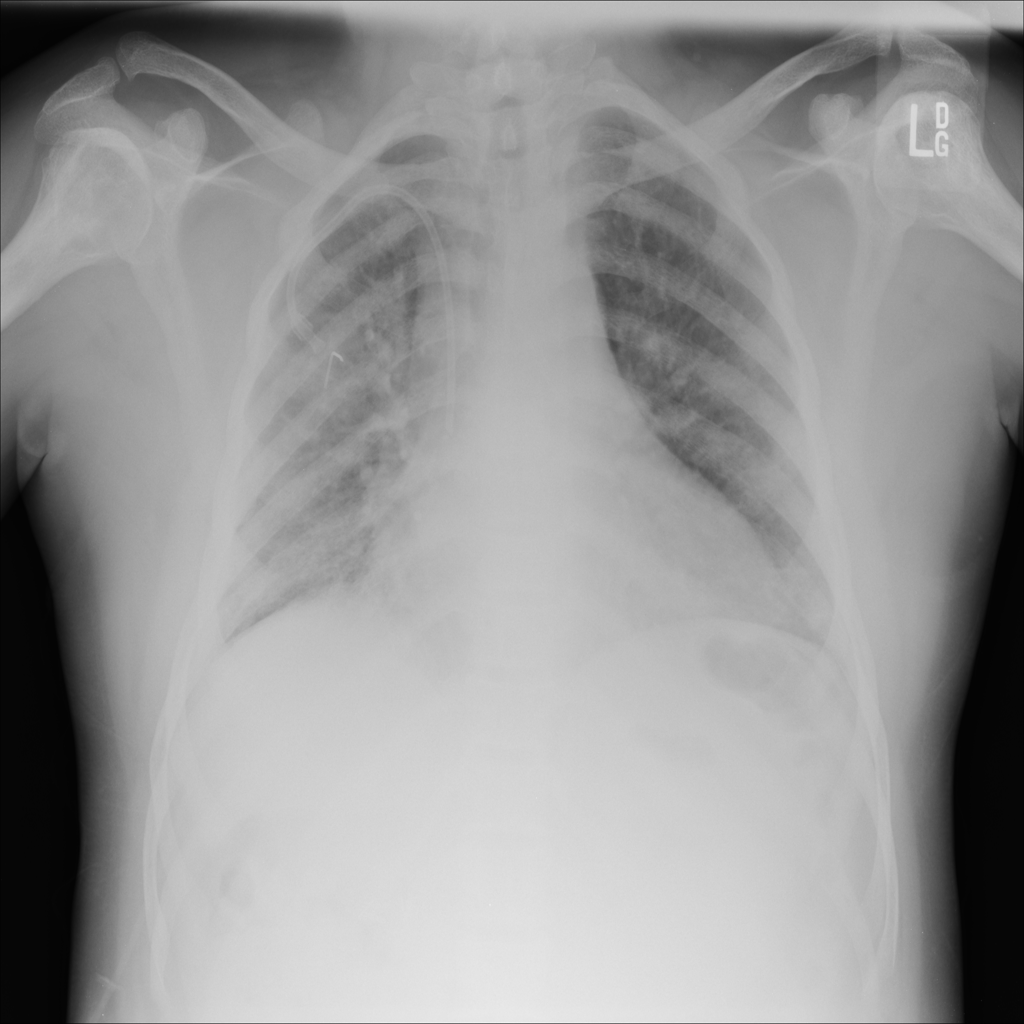

PAT-B3C3 · IMG-001Pneumonia

PAT-B3C3 · IMG-001

PA